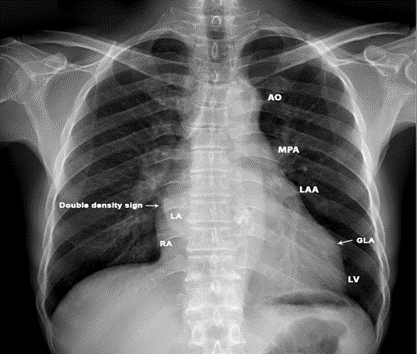

Case 2. PML (posterior mitral leaflet) prolapse causing severe mitral regurgitation with aneurysmal LA (left atrium) as shown in Figures 3 to 8 due to PML chordal rupture of rheumatic etiology in a 47- year old male. Patient was advised lifelong penicillin prophylaxis and MVR (mitral valve replacement).

Figure 3. X-ray chest PA (postero-anterior) view showing the “4-bump” left heart border as AO (aortic knuckle), MPA (Main pulmonary artery), LAA (dialed convex left atrial appendage (third mogul sign)), LV (left ventricle). Aneurysmal left atrium elevating the left main stem bronchus which becomes more horizontal and a ‘double density sign in the right heart border (right arrow). Left arrow- showing the GLA (giant left atrium) reaching towards left chest wall.